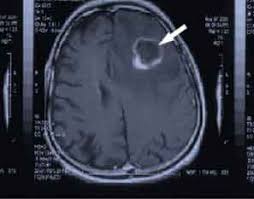

Cancer research has been blown out of proportion in that medical

professionals are trying all kinds of research to have tumors retreat without

evasive surgeries.

They are now killing cancer in

your brain. In previous years a courageous doctor would crack your skull and

try to cut the tumor out or just give you a set time of expectancy to live. Now

little hope for much of a future. The doctors use 3-D MRI scanning to plot

their descent into the brain with the Polio. Like a snipers bullet, if it doesn’t

go to the center, it will not kill its target that tumor.